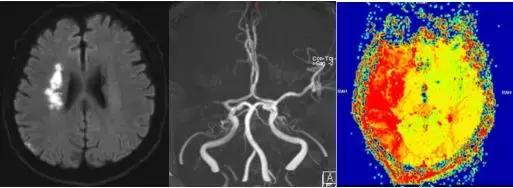

磁共振提示脑梗死,右侧大脑中动脉闭塞

这次,杨叔叔来到郑州市中心医院,复查核磁共振显示,他又出现的新的脑梗死区域

一系列检查显示,杨叔叔这次脑梗死比之前面积大,但存在可挽救的脑组织!

磁共振提示大面积脑缺血,存在可挽救的脑组织